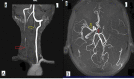

Takayasu's arteritis is a chronic inflammation of the large arteries such as the aorta and its primary branches, causing progressive arterial occlusion. This leads to reduced blood flow in the limbs and organs, resulting in arm or leg claudication, diminished or absent peripheral pulses, and end-organ ischemia. Stroke is one of the common complications; however, it is rarely the initial presentation. We describe one such case of a 16-year-old female, who presented with right-sided hemiparesis and non-fluent aphasia, without any significant past history. On examination, her right arm was cold and pulseless. She was extensively investigated for the cause of her presentation. Only non-specific inflammatory markers such as erythrocyte sedimentation rate (ESR) were elevated. Imaging studies revealed left middle cerebral artery territory infarct with occlusion of common carotid arteries, bilateral bifurcation, most parts of the left internal carotid artery, and the proximal part of the right internal carotid artery. She was diagnosed with Takayasu's arteritis and was prescribed steroids, on which she gradually recovered and was discharged. In conclusion, young patients, who present with stroke, should be investigated for Takayasu's arteritis, which leads to earlier treatment and prevention of further life-threatening end-organ damage.